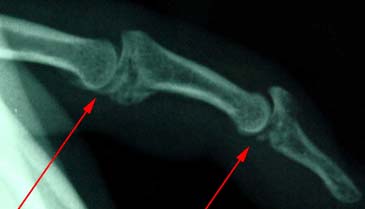

Fractures within the finger joints.